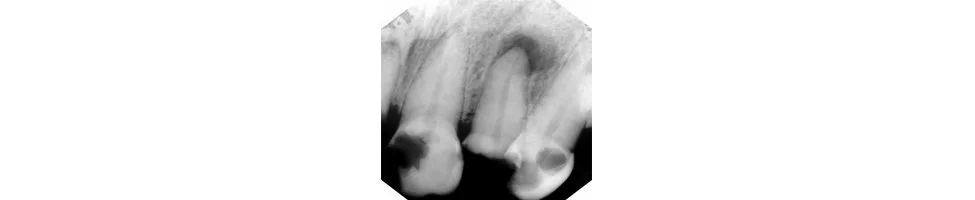

• Poor bone support as a result of Periodontal Disease.

• Severe decay.

• Root fractures.